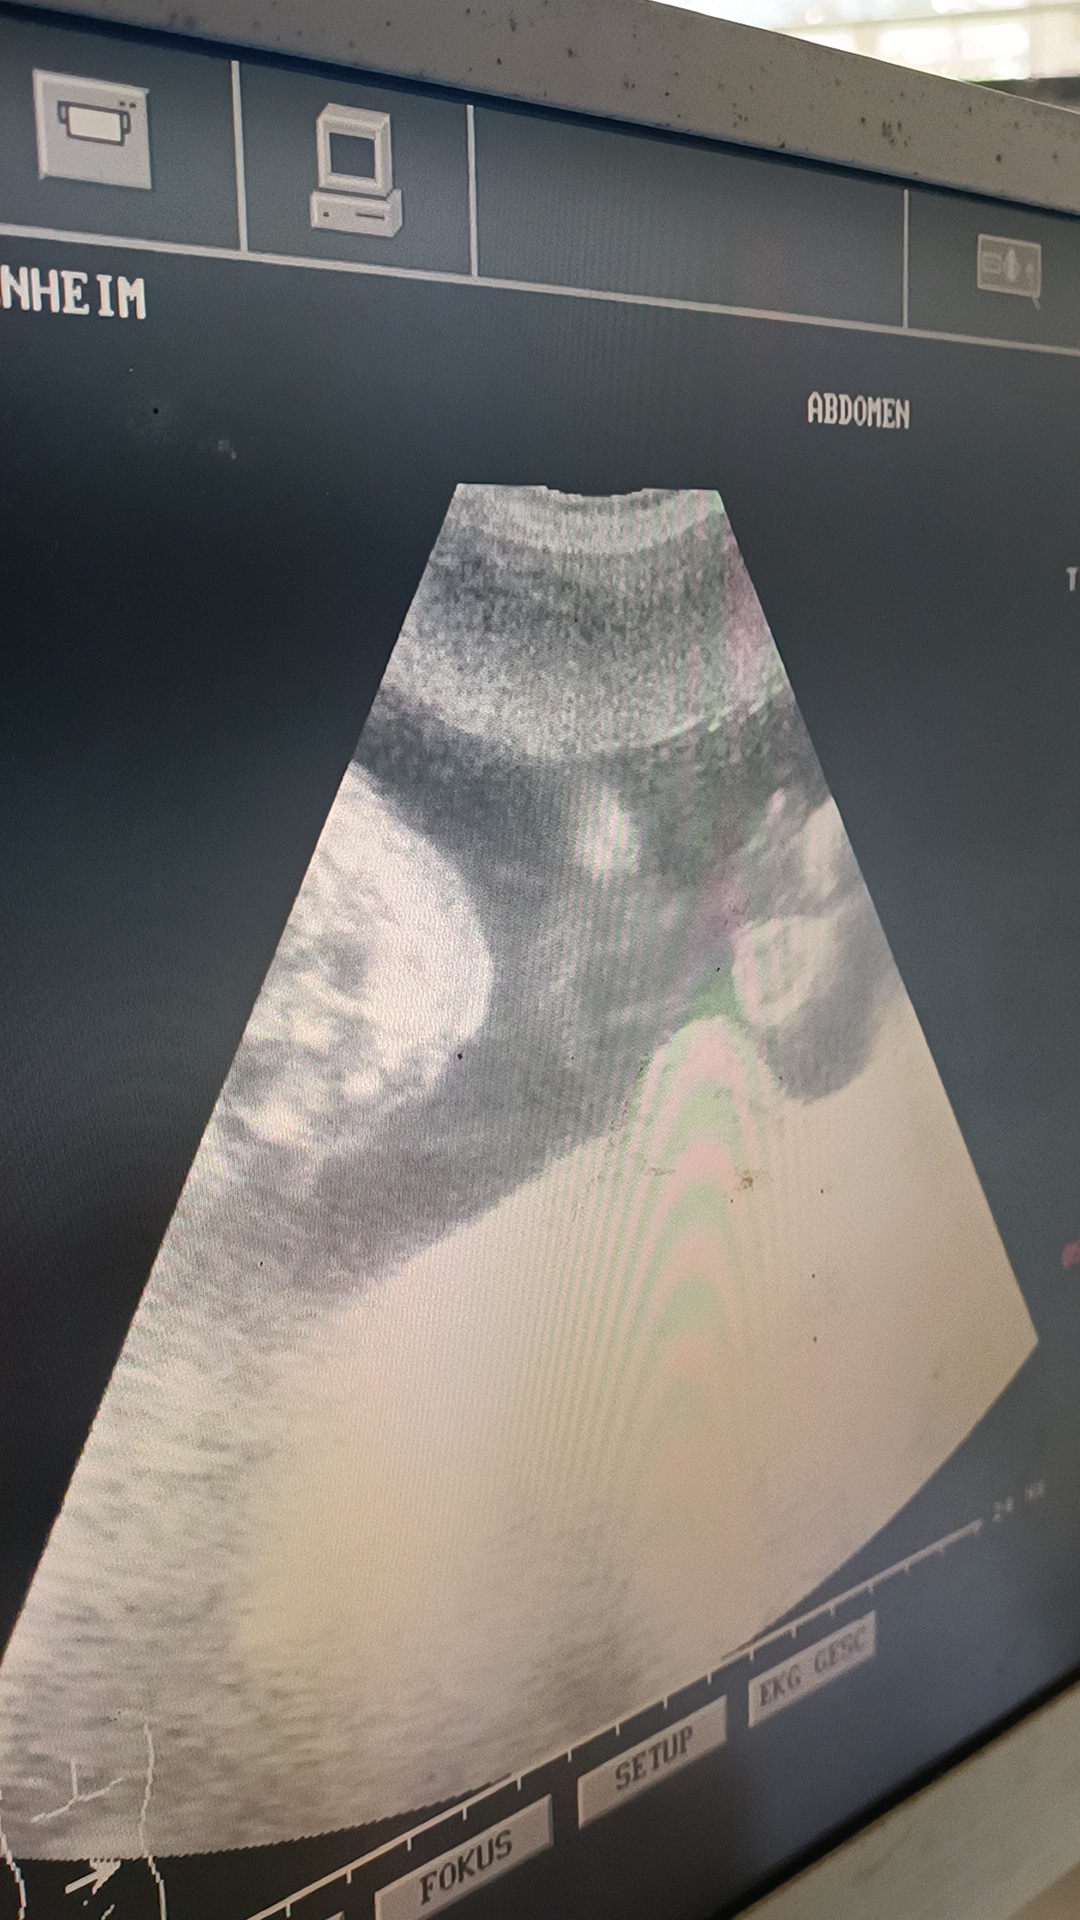

As a highlight, an ultrasound was offered for the pregnant women:

A German midwife, who regularly does team training for obstetrics, was once again in Kenya and carried out the ultrasound examinations on the women.